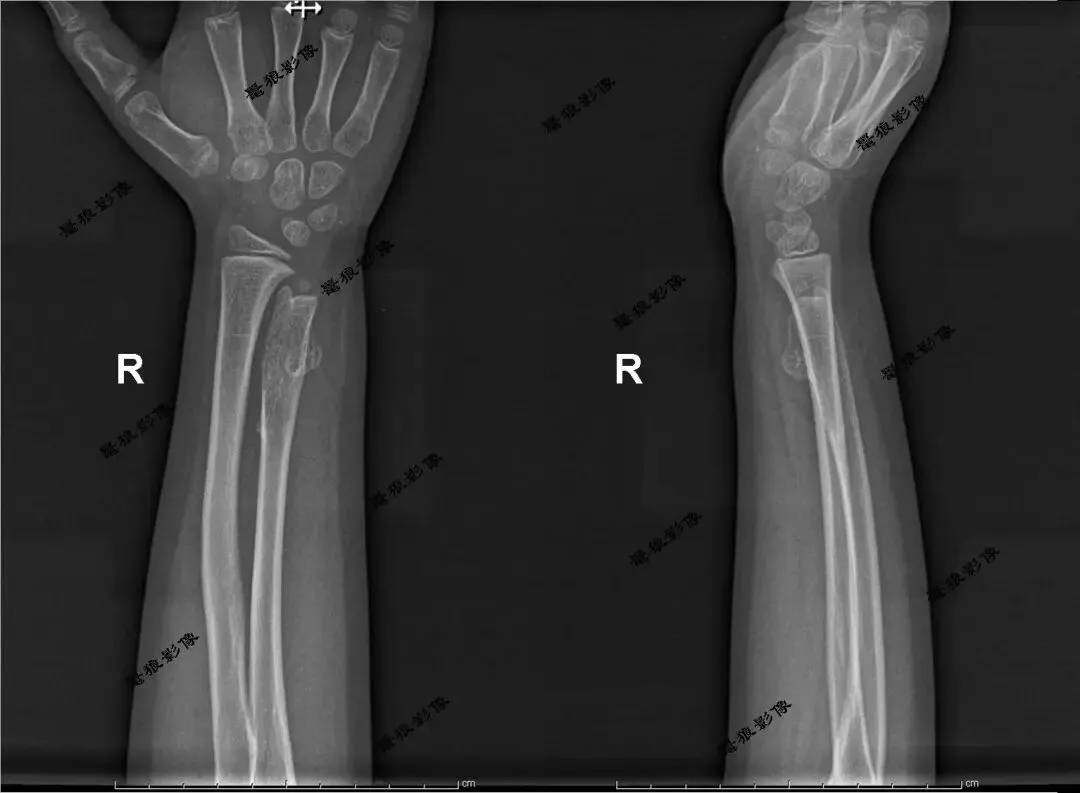

M,7y。双腕及双膝周围多处隆起就诊。

双腕关节及双膝关节X线片如下图:

考虑双腕关节及双膝关节旁多发骨软骨瘤,右膝为甚。